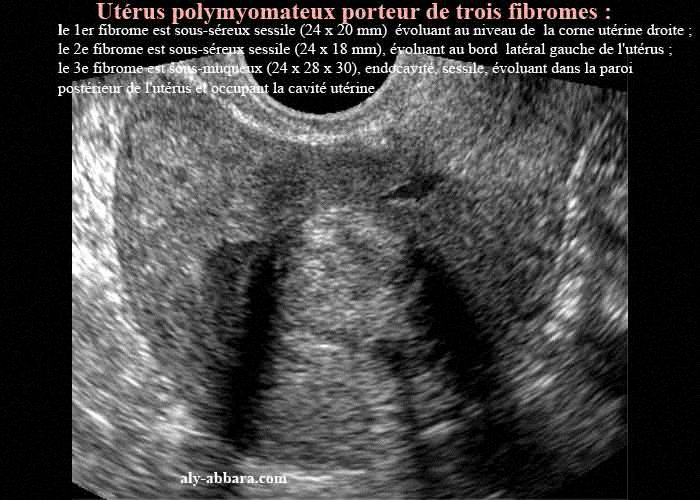

Utérus polymyomateux, porteur de trois myomes

• Deux myomes sous-séreux sessiles (sur les coupes transversales) :

• le 1er fibrome est sous-séreux sessile (24 x 20 mm) évoluant au niveau de la corne utérine droite ;

• le 2e fibrome est sous-séreux sessile (24 x 18 mm), évoluant au bord latéral gauche de l'utérus ;

• le 3e fibrome (sur la coupe sagittale et les coupes transversales) est sous muqueux (24 x 28 x 30), endocavité, sessile, évoluant dans la paroi postérieur de l'utérus et occupant la cavité utérine.

Ce dernier fibrome est à l'origine de ménorragies sévères, avec une anémie à 7 - 8 g par dl, presque à chaque règles.